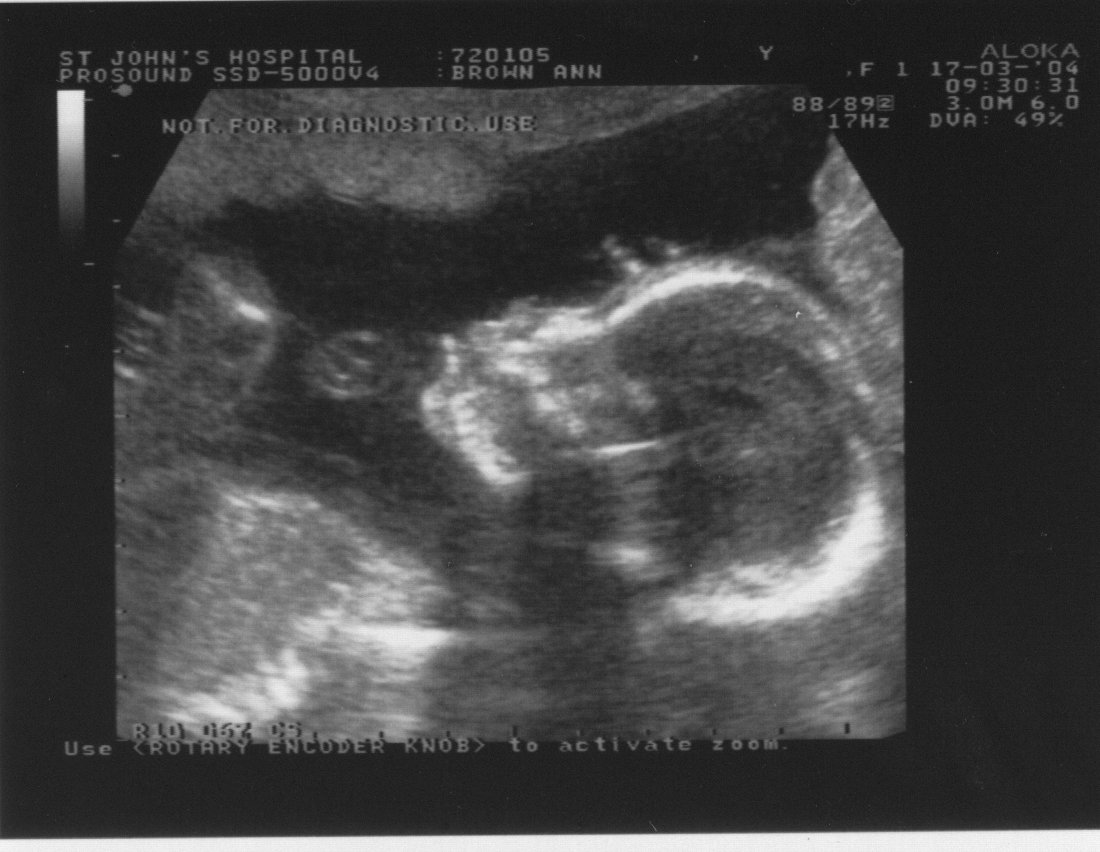

17th March 2004 (21 weeks)